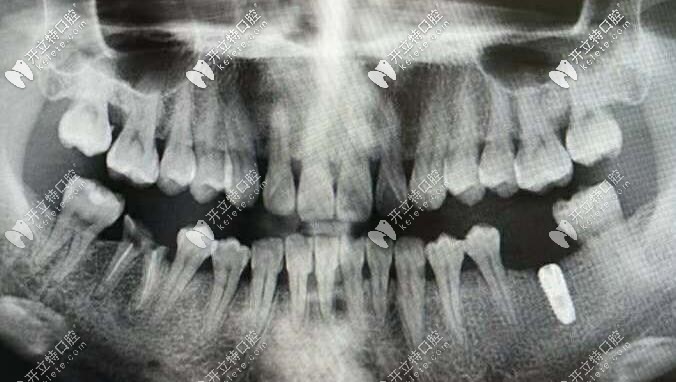

韓國(guó)inno種植體

先為大家簡(jiǎn)單介紹一下韓國(guó)inno種植體吧!

韓國(guó)伊諾種植體種植體在近幾年內(nèi)慢慢進(jìn)入市場(chǎng),一經(jīng)使用便受到了廣大顧客的一致認(rèn)可。伊諾種植體是經(jīng)過(guò)了FDA、CE、CFDA等認(rèn)證的種植體,不管是安全性還是性能方面,都有著不錯(cuò)的表現(xiàn)。